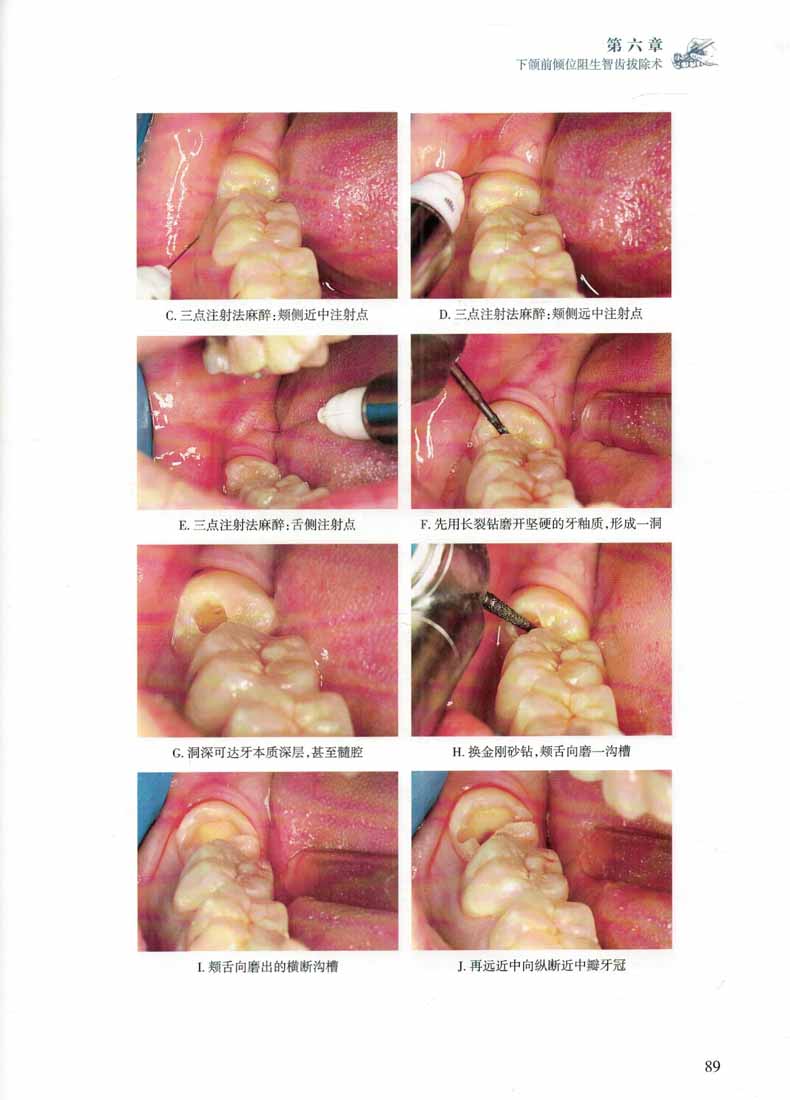

本書一改傳統翻瓣鑿骨法拔除阻生智齒的手術思路,基於作者數十年拔除智齒的臨床經驗提出了渦輪鑽法拔除阻生智齒的手術思路,即:以潛鑽法先分牙、多分牙,以三角切齦代替翻瓣或小翻瓣,少去骨、不去骨或不首先去骨的地拔除阻生智齒。較之傳統方法,不僅降低了術者的操作難度,也在很大程度上減少了患者拔牙後的創傷及並發症。對相關臨床工作者有很大的實際指導意義。書中詳細闡述了應用該法拔除各類阻生智齒的具體步驟。本版不僅延續上版特色附大量精美圖片,圖文並茂,且在上版基礎上新增23個高清拔牙手術視頻,紙數融合,讀者可通過掃描二維碼形式輕鬆觀看。力求為廣大口腔醫師提供一冊專業 、內容實用、易讀易學的參考書。